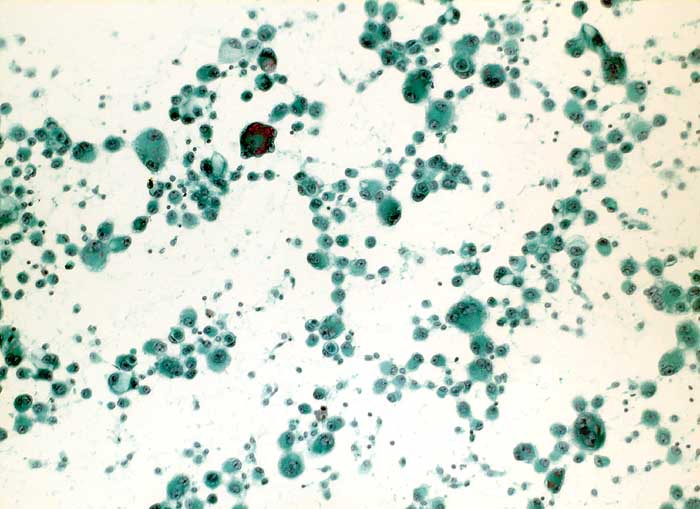

PathoPic – image database / PathoPic ID 6193 - nicht kleinzelliges Bronchuskarzinom

nicht kleinzelliges Bronchuskarzinom

Pleuraerguss Zytologie

Pleuraerguss: massenhaft Zellen eines Adenokarzinoms. Die extreme Polymorphie mit sehr unterschiedlich grossen Tumorzellen passt zu einem primären Lungenkarzinom.

Metastasierendes Bronchuskarzinom

Zytologie

100